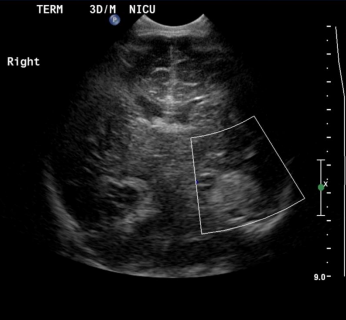

Ultrasound head showed left temporal lobe increased echogenicity with loss of normal gray-white matter differentiation with no flow on Doppler interrogation most likely represent hemorrhage. (Fig. 1). MRI scan was done on day 6 showed extra axial hemorrhage with high signal intensity on T1-weighted images and low signal intensity on T2-weighted images in the left temporal lobe opposing the underlying sulci and separate from the adjacent CSF (Fig. 2A and B). It showed mass effect on the adjacent cortex with cortical high signal intensity on T1 and T2-weighted images with evidence of diffusion restriction (Fig2 C, D). The final diagnosis was subpial hemorrhage with adjacent cortical hemorrhagic infarction.

Figure 1